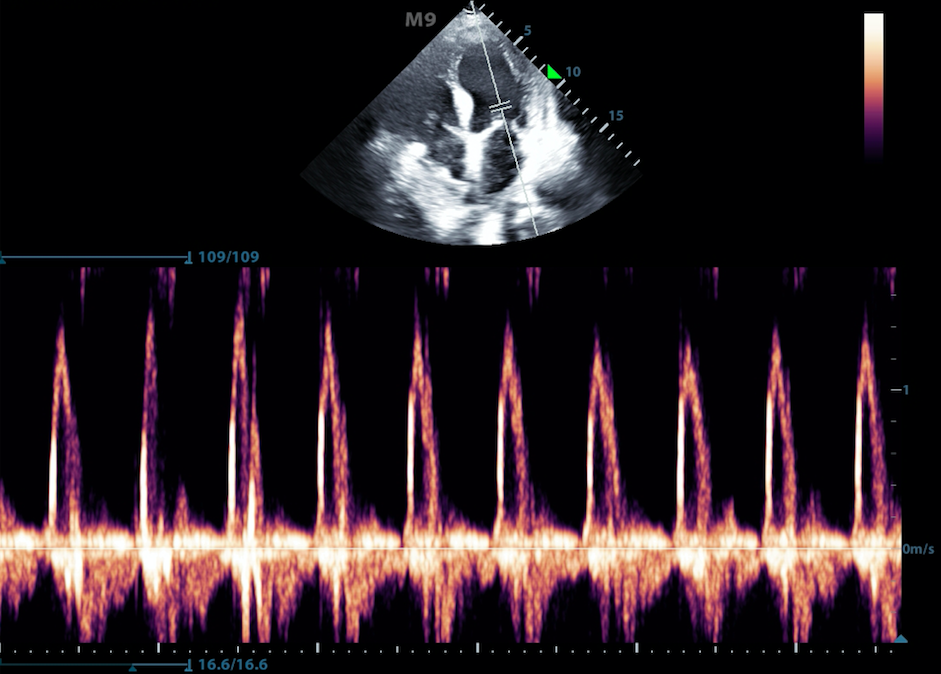

- Often M-mode and B-mode are displayed together in real-time on the ultrasound monitor (Figure 2, Video 1)

- Figure 2. M-Mode (lower portion of the image) combined with B-Mode image. In this still image the M-mode captures the movement of a particular part of the heart.)

Video 1. M-Mode showing movement of the mitral valve